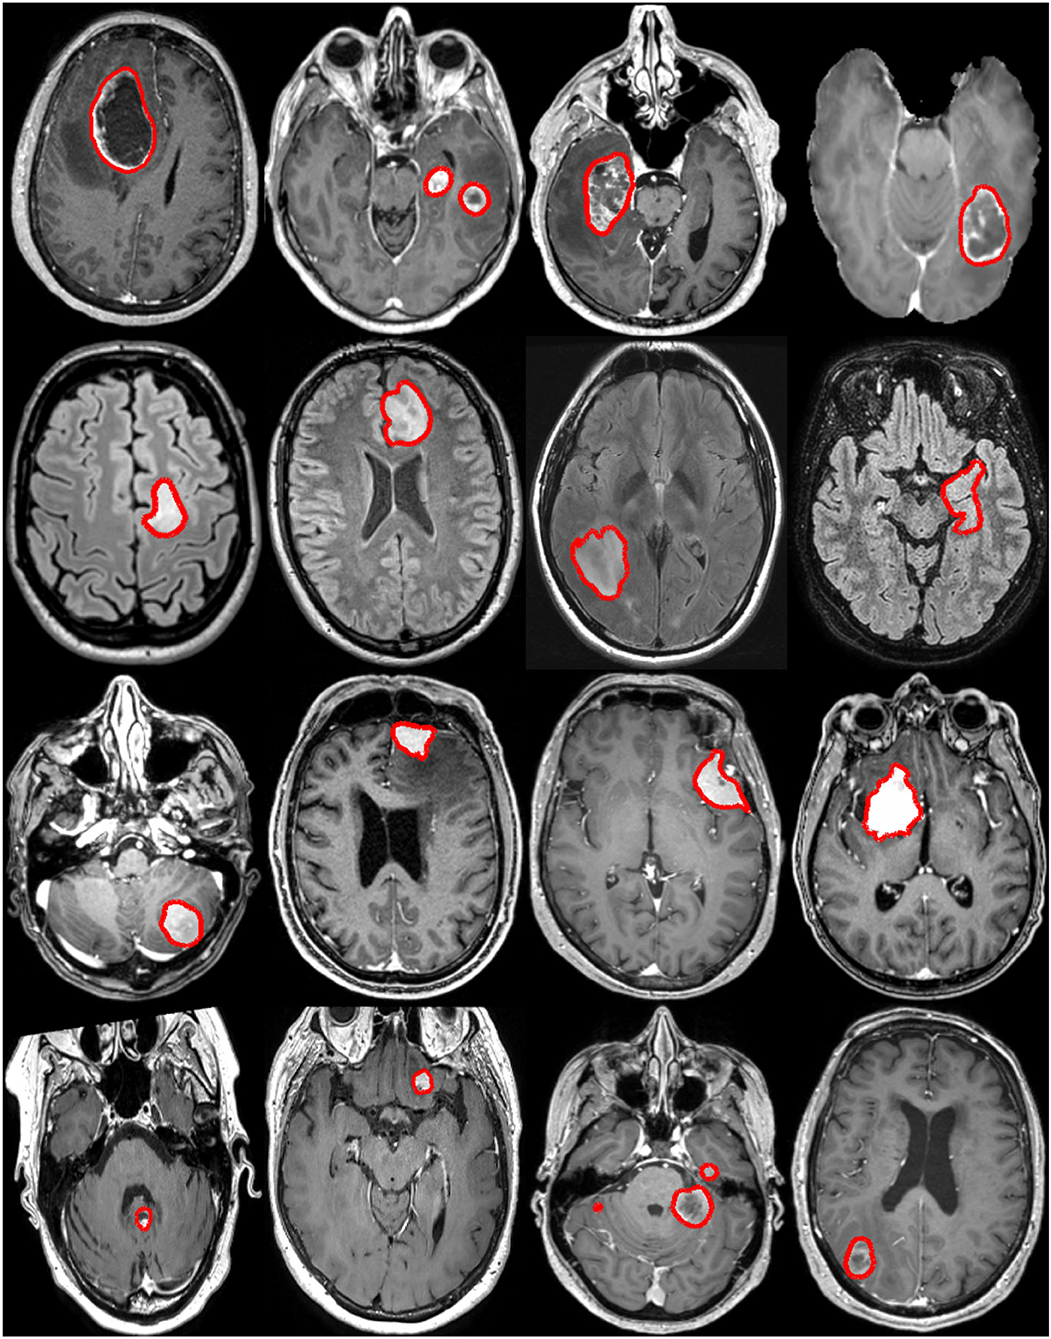

Brain Cancer Mri

Figure Brain MRI With And Without Contrast Download Scientific Diagram

https://www.researchgate.net/publication/344282508/figure/fig1/AS:11431281081111555@1661533445082/Figure-Brain-MRI-With-and-Without-Contrast.ppm